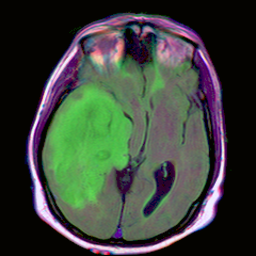

The following example uses the U-Net for brain segmentation model trained to detect lower-grade gliomas to demonstrate how to:

We will perform a test inference by converting the file TCGA_CS_4944.png into a numpy array, and setting that as a row in a DataFrame for our inference request.

input_image = Image.open("./data/TCGA_CS_4944.png")